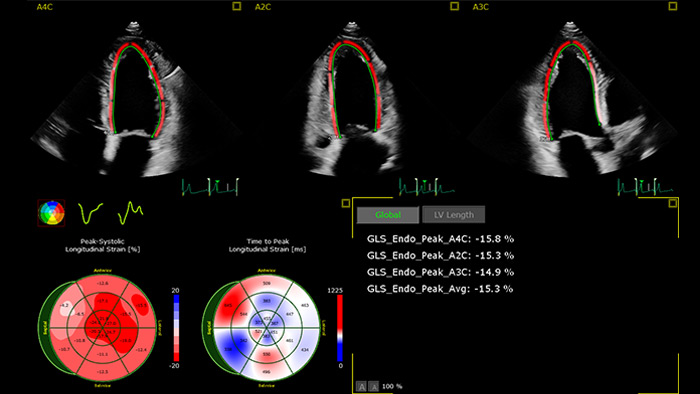

Automatische GLS-Messung für die klinische Routine-Anwendung

Die in das Verfahren integrierte oder bei der Nachverarbeitung angewendete Funktion AutoStrain bietet eine einfache und schnelle GLS-Messung mittels Auto View Recognition und Auto Contour Placement. AutoStrain LV basiert auf einer Lernkurve von mehr als 6000 Bildern und bietet somit Zuverlässigkeit und eine reproduzierbare linksventrikuläre Strain-Messung bei der täglichen klinischen Anwendung.